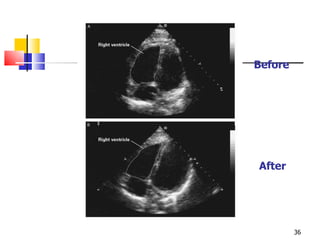

Before After